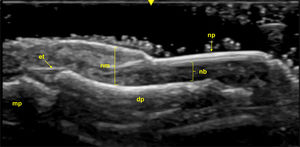

Ultrasound imaging identifies three primary structures of the nail apparatus: the nail plate, the nail bed, and the nail matrix. The nail plate consists of two parallel hyperechoic layers, separated by a hypoechoic interlaminar space, with normal thickness ranging between 0.3 and 0.65mm. The nail bed, a hypoechoic structure located between the ventral plate and the periosteum of the distal phalanx, measures between 0.7 and 6.5mm in thickness. The nail matrix, located proximally, appears isoechogenic and measures 1–5.3mm in length [134] (Fig. 5).

Fig. 5.Healthy Nail (Longitudinal View): Sonographic image obtained using Logiq e US system with an 8–18i MHz linear transducer. The nail plates (np) appear as two parallel hyperechoic layers, separated by a hypoechoic interlaminar space. The nail matrix (nm) is visible as an isoechogenic structure located proximally, while the nail bed (nb) is shown as a hypoechoic area between the ventral nail plate and the periosteum of the distal phalanx (dp). The extensor tendon (et) inserts distally at the base of the dp. mp=middle phalanx.